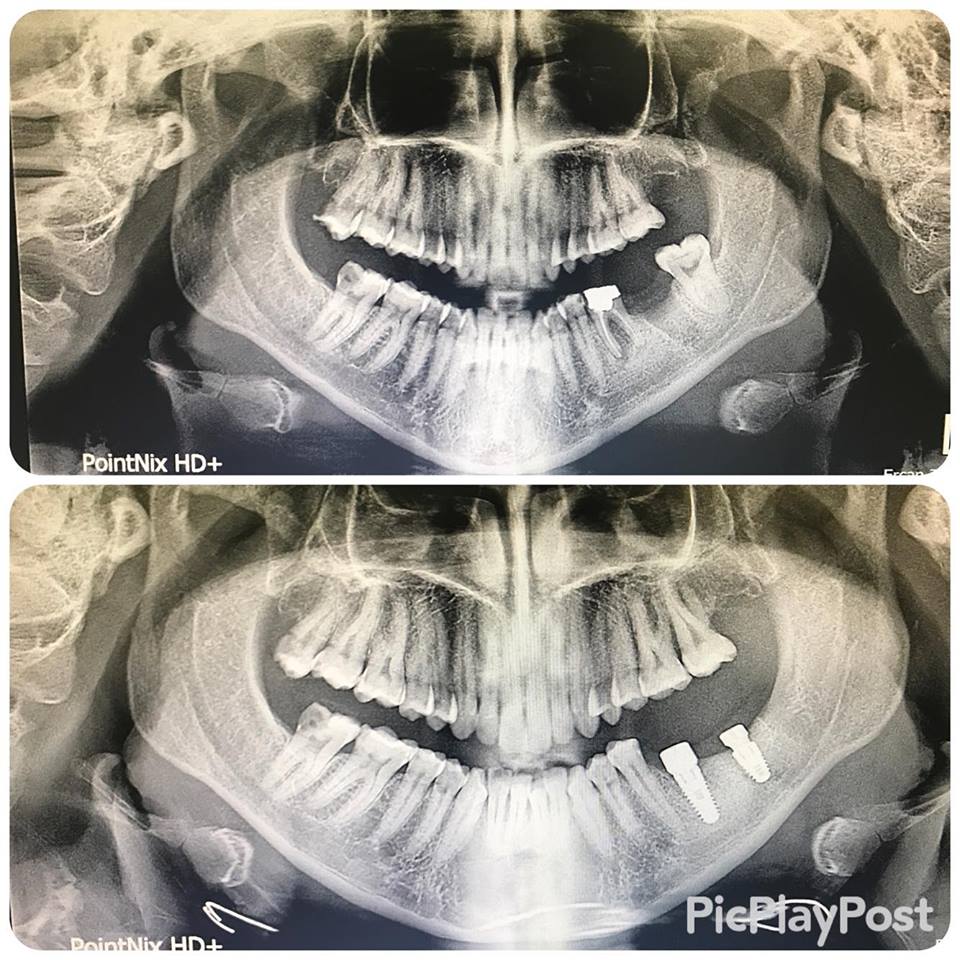

İMPLANT TEDAVİSİ

implant tedavisi